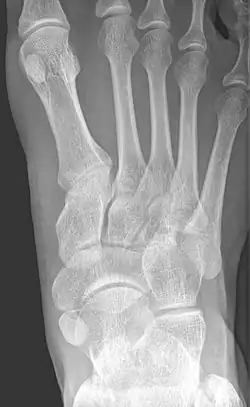

Cornuate navicular bone